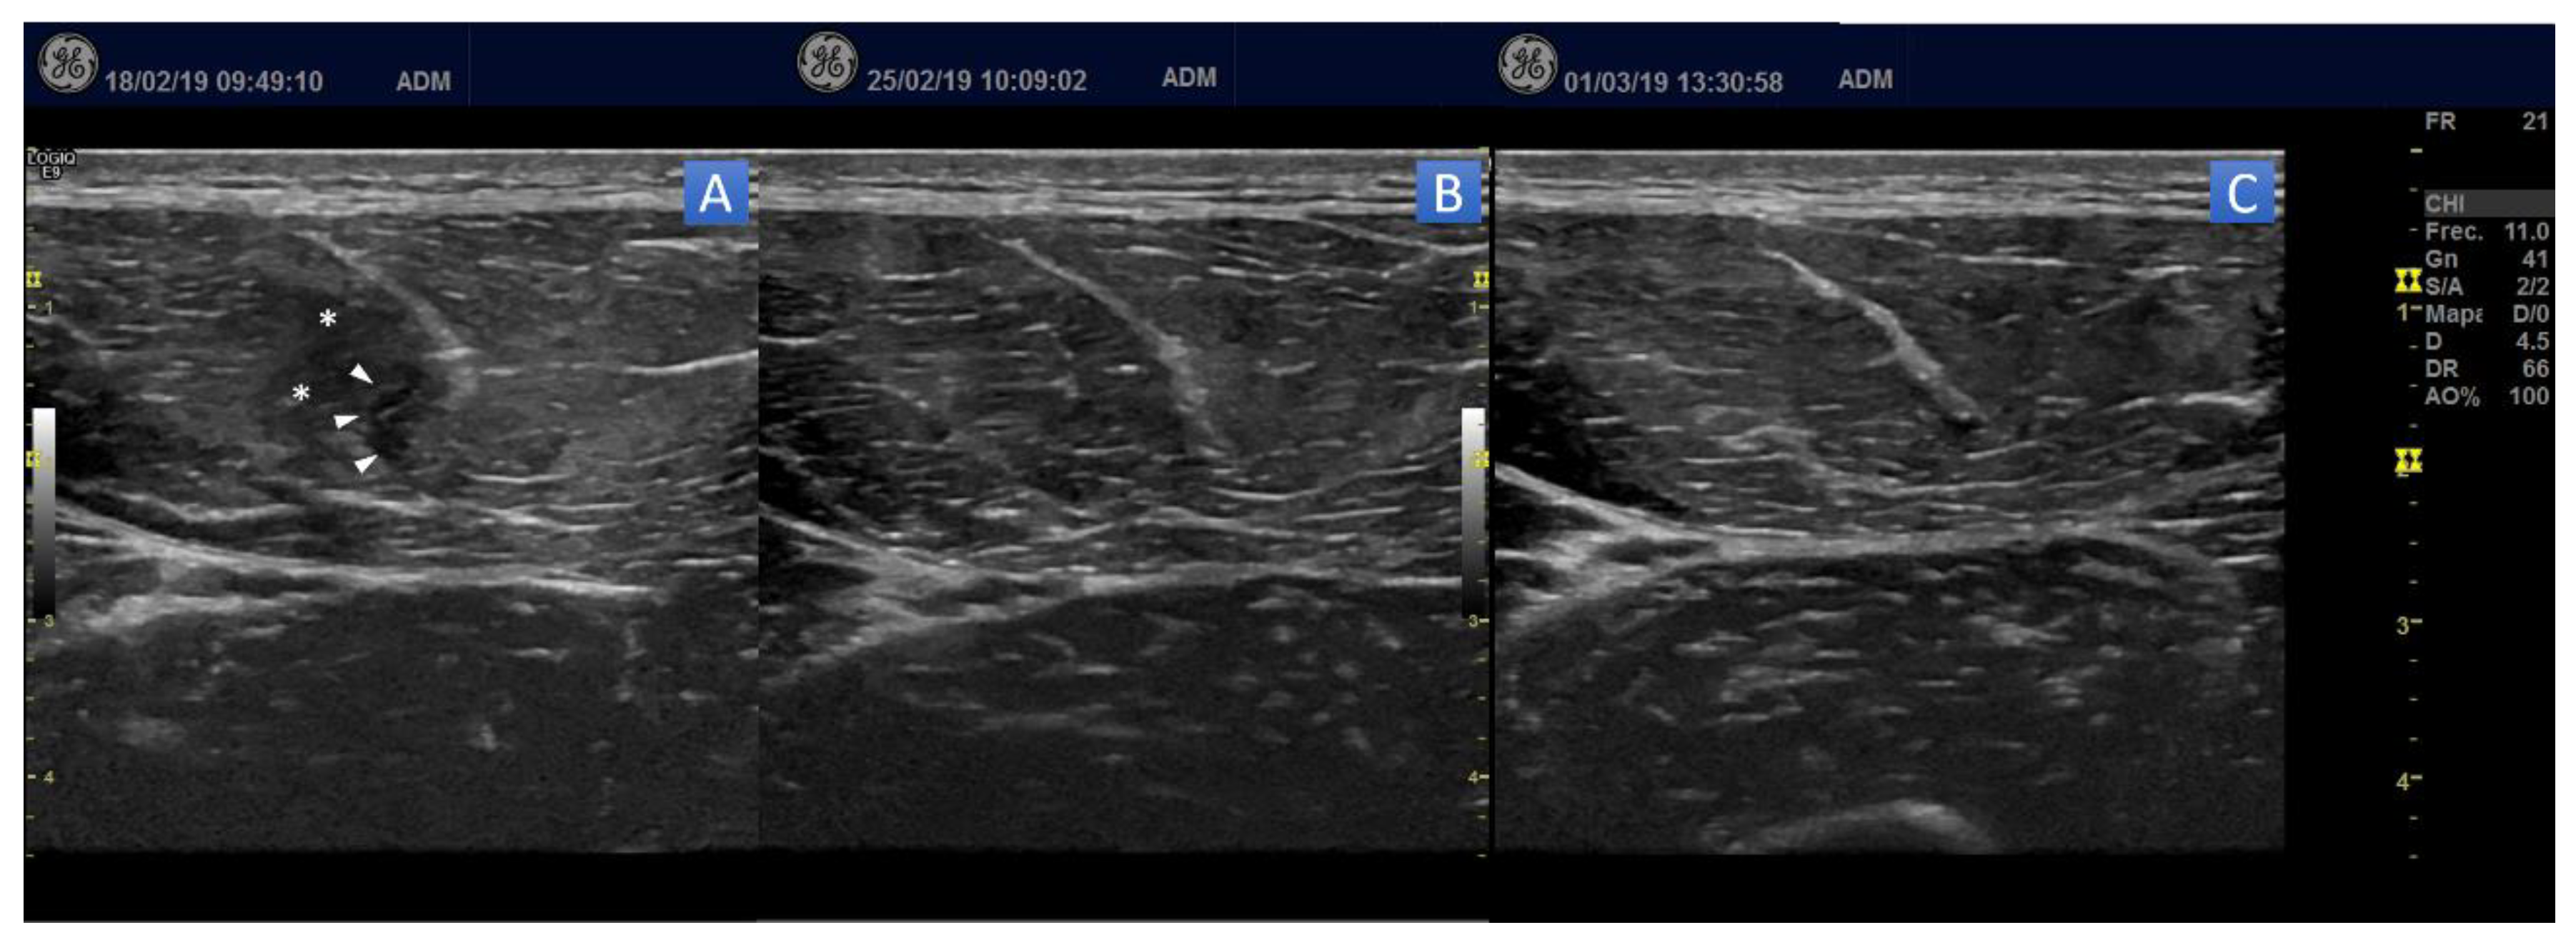

5.1. Ultrasound